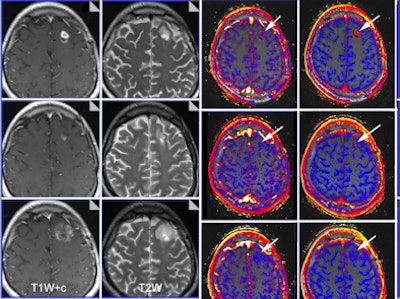

| Functional imaging biomarkers can provide important clinical information. In this case, multiparametric MRI was used to evaluate brain glioma response to bevacizumab therapy. Columns: T1-weighted images with contrast; T2-weighted images; transfer constant and leakage space. Rows (from the top): baseline, 10 days of therapy, and six weeks of therapy. Note that morphology imaging shows an initial response by the 10th day, but the tumor then progresses and is much larger at six weeks. However, functional images show that the drug is still working (reductions of transfer constant and leakage space - arrows). Images courtesy of Dr. Anwar Padhani, Paul Strickland Scanner Centre, Mount Vernon Cancer Centre, London. The images have been published in part in the following article: Padhani AR, Miles KA. Multiparametric imaging of tumor response to therapy. Radiology. 2010; Vol. 256:2, pp. 348-364. |

Overall, they think imaging plays a critical role in all aspects of personalized medicine: prediction, diagnosis, and especially treatment. Imaging is essential for excellent personalized medicine because it is the only patient-friendly means to obtain information on location, especially with regard to heterogeneous expression within an individual patient. Furthermore, imaging can also provide details about expression patterns, perfusion, metabolic activity, etc., which can be pivotal in deciding what the best treatment is and when is the best time to give it, the authors explained.